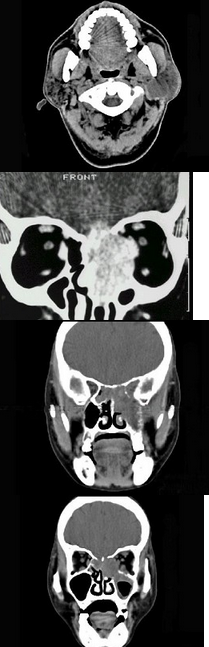

2、单项选择题

男,65岁,左眼球突出近一年,鼻涕带血,面颊部隆起,同时面颊部有麻木感,CT检查如图,最可能诊断为()

A.上颌窦息肉

B.上颌窦血管瘤

C.上颌窦囊肿

D.上颌窦癌

E.骨肉瘤